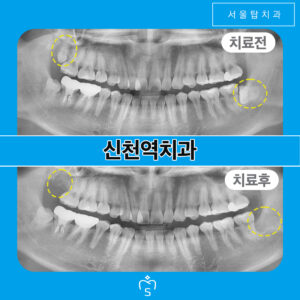

시흥신천동치과 사랑니로 인해 앞의치아를 발치하고

시흥신천동치과 사랑니로 인해 앞의치아를 발치하고   사랑니는 사람에 따라 1~4개가 맹출 할 수도 있고, 하나도 맹출 하지 않는 경우도 있는데요.   사랑니가 올바르게 맹출 하여 저작에 도움이 되고 관리가 잘 된다면 발치를 하지 않아도 되지만,   보통은 맨 안쪽에 자리 잡고 있어 위생관리가 어렵고, 충치, 치주 질환 등의 문제에 취약하기에 더보기…